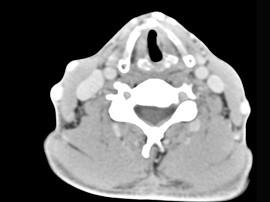

问题 男性,50岁,自觉咽喉部不适1个多月,间或刺激性咳嗽,CT扫描如图所示,请选择正确的描述和答案 ( )

选项 A、考虑为左侧声带乳头状瘤 B、考虑为喉癌 C、增强扫描结节强化不明显,密度均匀,周围结构未见受侵 D、考虑为左侧声带息肉 E、左侧声带内侧壁见结节状影向腔内突出,以宽基底与声带相连

答案 ACE